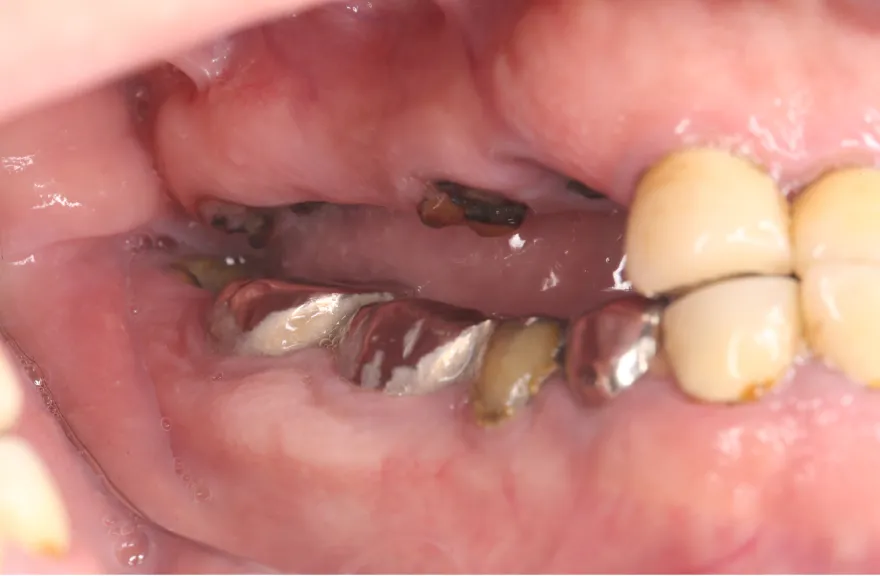

今まで何回歯を入れてもトラブルが起きるために、奥の歯を入れないまま今日に至る、ということでした。

噛み合わせ・骨格を読み解き、今後の人生でトラブルが起きにくいように全体的な治療計画を練りました。 - 治療費用・方針

骨格の前後的な差がある方でした。術前のレントゲンより、上下で歯牙の損傷に明らかな差があるのがみてとれます。

しかし、治療において重要なのは今目の前の歯を見ることではなく、なぜ目の前の歯になったかを考え、未来へ活かすことです。

骨格的な前後差を考慮することなく歯をいれても、装着した人工物は決して長持ちしません。

今回の症例では、敢えて上顎は総義歯形態をとり、骨格的な前後の差を解消するよう工夫しました。

上顎の残っていた歯も、差し歯としては使えずとも、敢えて根だけ残すことによって組織を温存し、義歯の安定に寄与するよう設計しました。